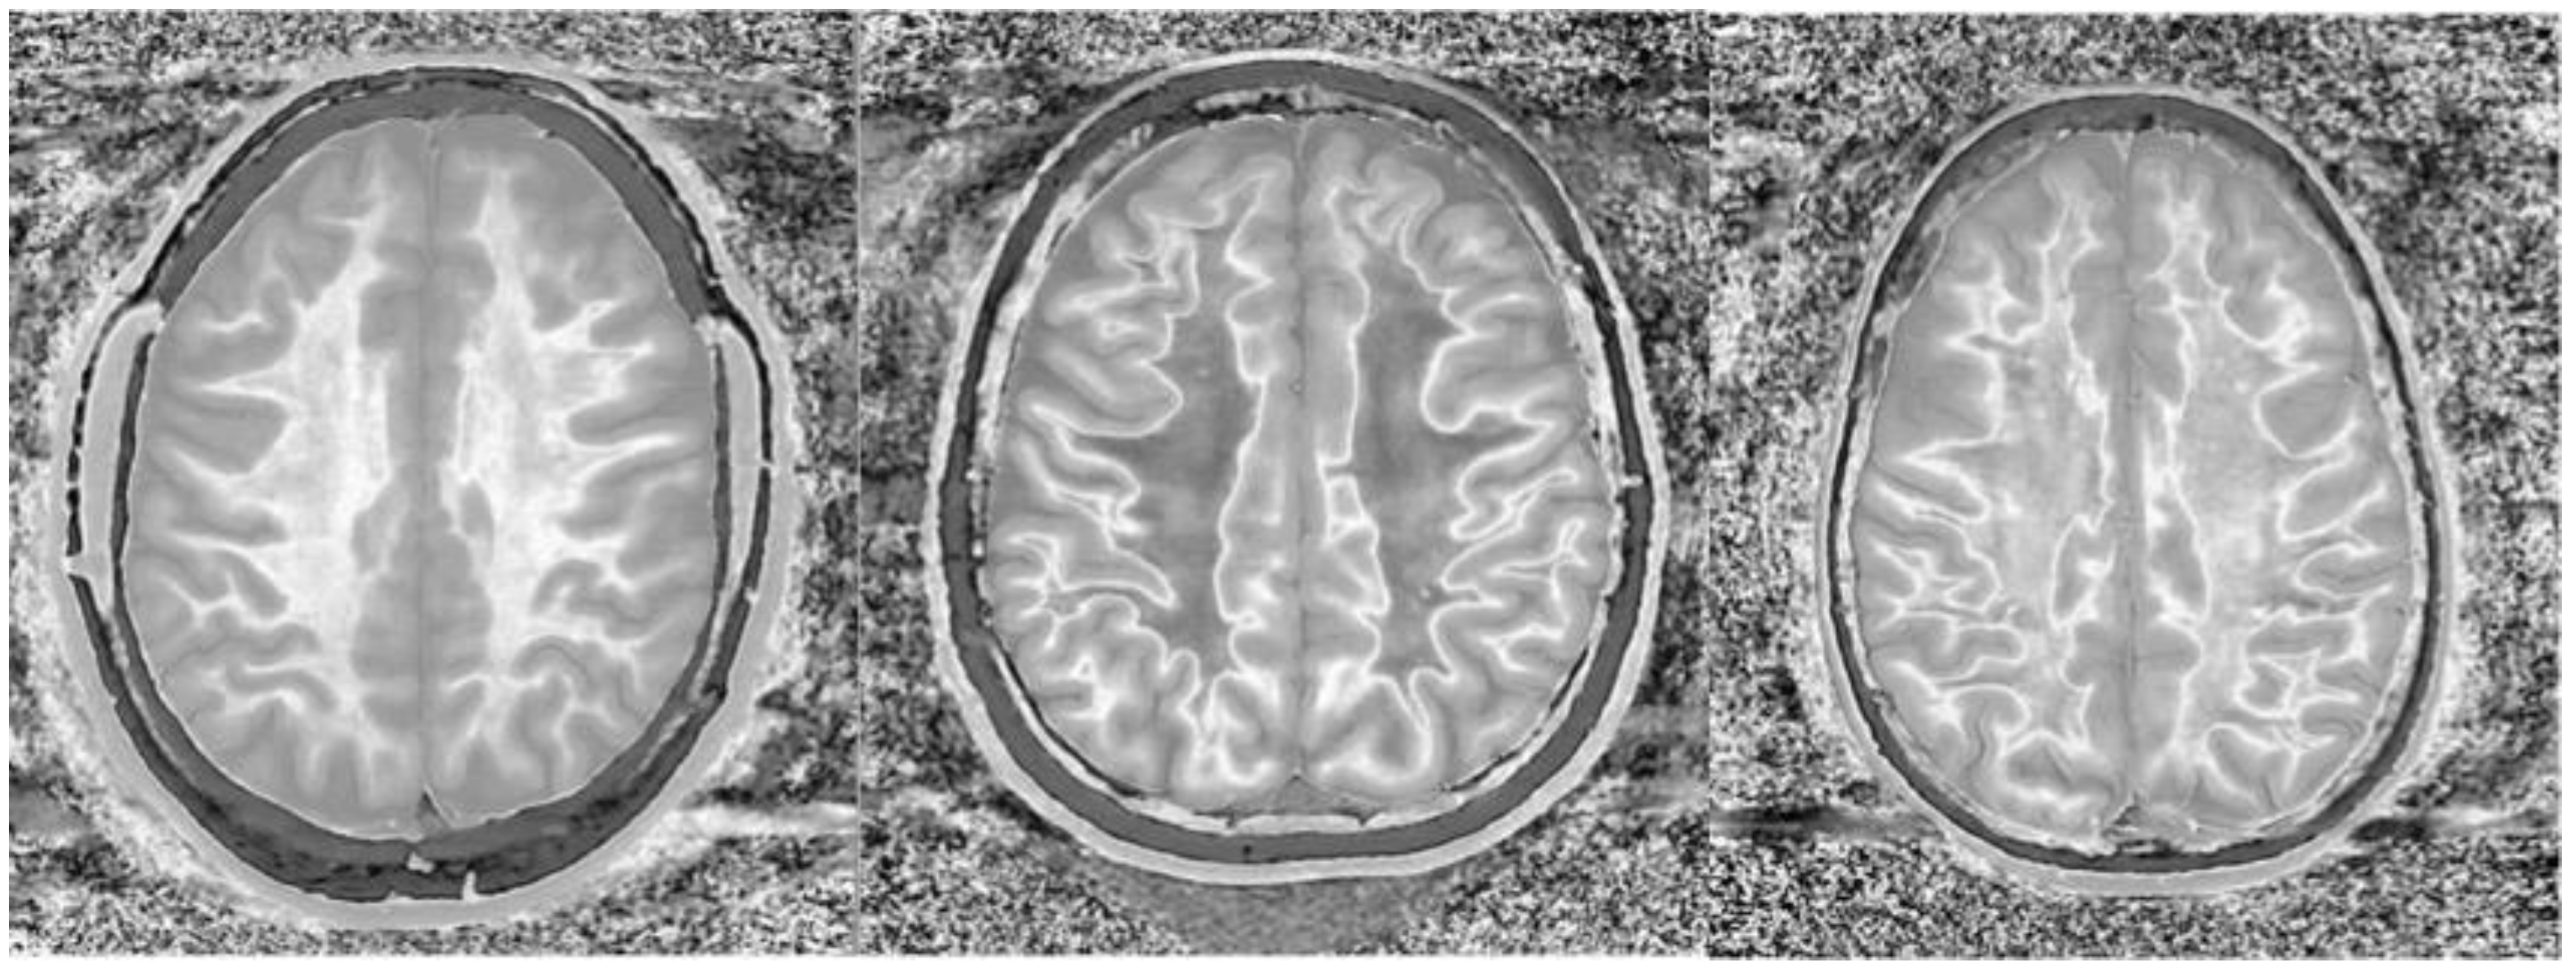

Figure 14.

Normal and abnormal divided Subtracted Inversion Recovery (dSIR) images. Narrow middle domain images in three patients at the level of the centrum semiovale. TIshort = 350 ms. TIlong = 500 ms. TE = 7 ms, TR = 5000 ms. The left image shows an example of the “white out sign”, with a diffusely increased signal throughout the white matter. The center image is an example of normal. The white matter has a mildly increased signal that is normal because TIshort = 350 ms nulls tissue with T1 values less than that of white matter. The image on the right has an intermediate appearance, probably abnormal but not a “white out”.